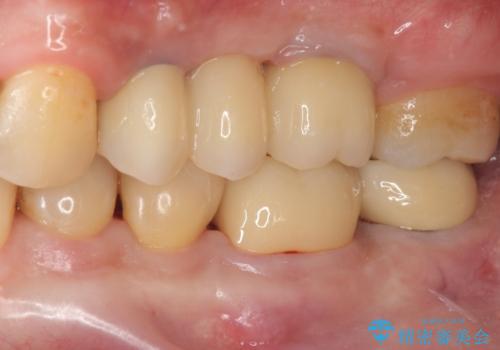

特定の歯に過大な力がかかることなく安定した咬合関係を構築できるよう治療計画を立案します。

咬合の調和、均等に力がかかることでより長期的な予後を期待することができます。

今回、左下6は頬側歯頚部に虫歯があり圧下を行ったことからクラウンにより補綴を行いました。